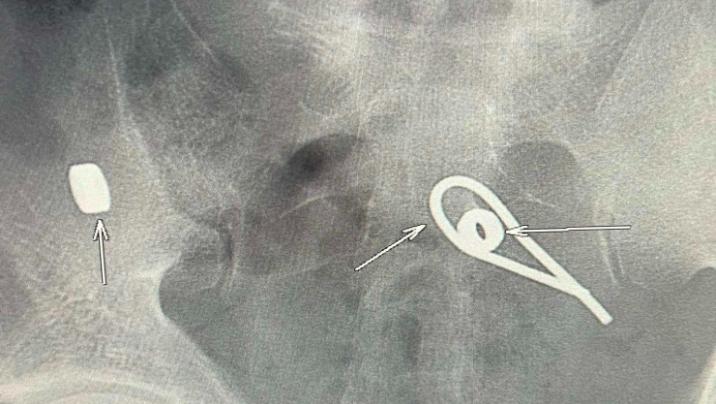

Stopnarkotik.az lent.az - a istinadən xəbər verir ki, bir kişi intihar etmək məqsədilə iki metal “qayka” və bir ədəd əyilmiş metal məftil udub.

O dərhal xəstəxanaya yerləşdirilib. Rentgen müayinəsi zamanı kişinin bağırsaqlarında udduğu metal parçalarının yeri müəyyənləşib. Hazırda həkimlər metalların çıxarılması üçün tədbirlər görür.